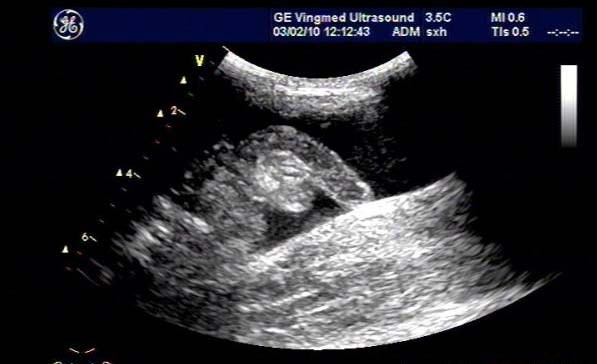

闌尾炎是美國兒童常見的疾病,發(fā)生率持續(xù)增加;雖然CT是最常用來評估疑似闌尾炎患者之癥狀的影像技術(shù),但它與顯著增加放射線暴露有關(guān),而超聲檢查不會(huì)有放射線暴露。

研究目標(biāo)是,兒童急性闌尾炎時(shí),使用超聲檢查作為第一種影像檢查方式時(shí),確認(rèn)是否會(huì)增加復(fù)雜性闌尾炎比率與住院天數(shù)(LOS)。